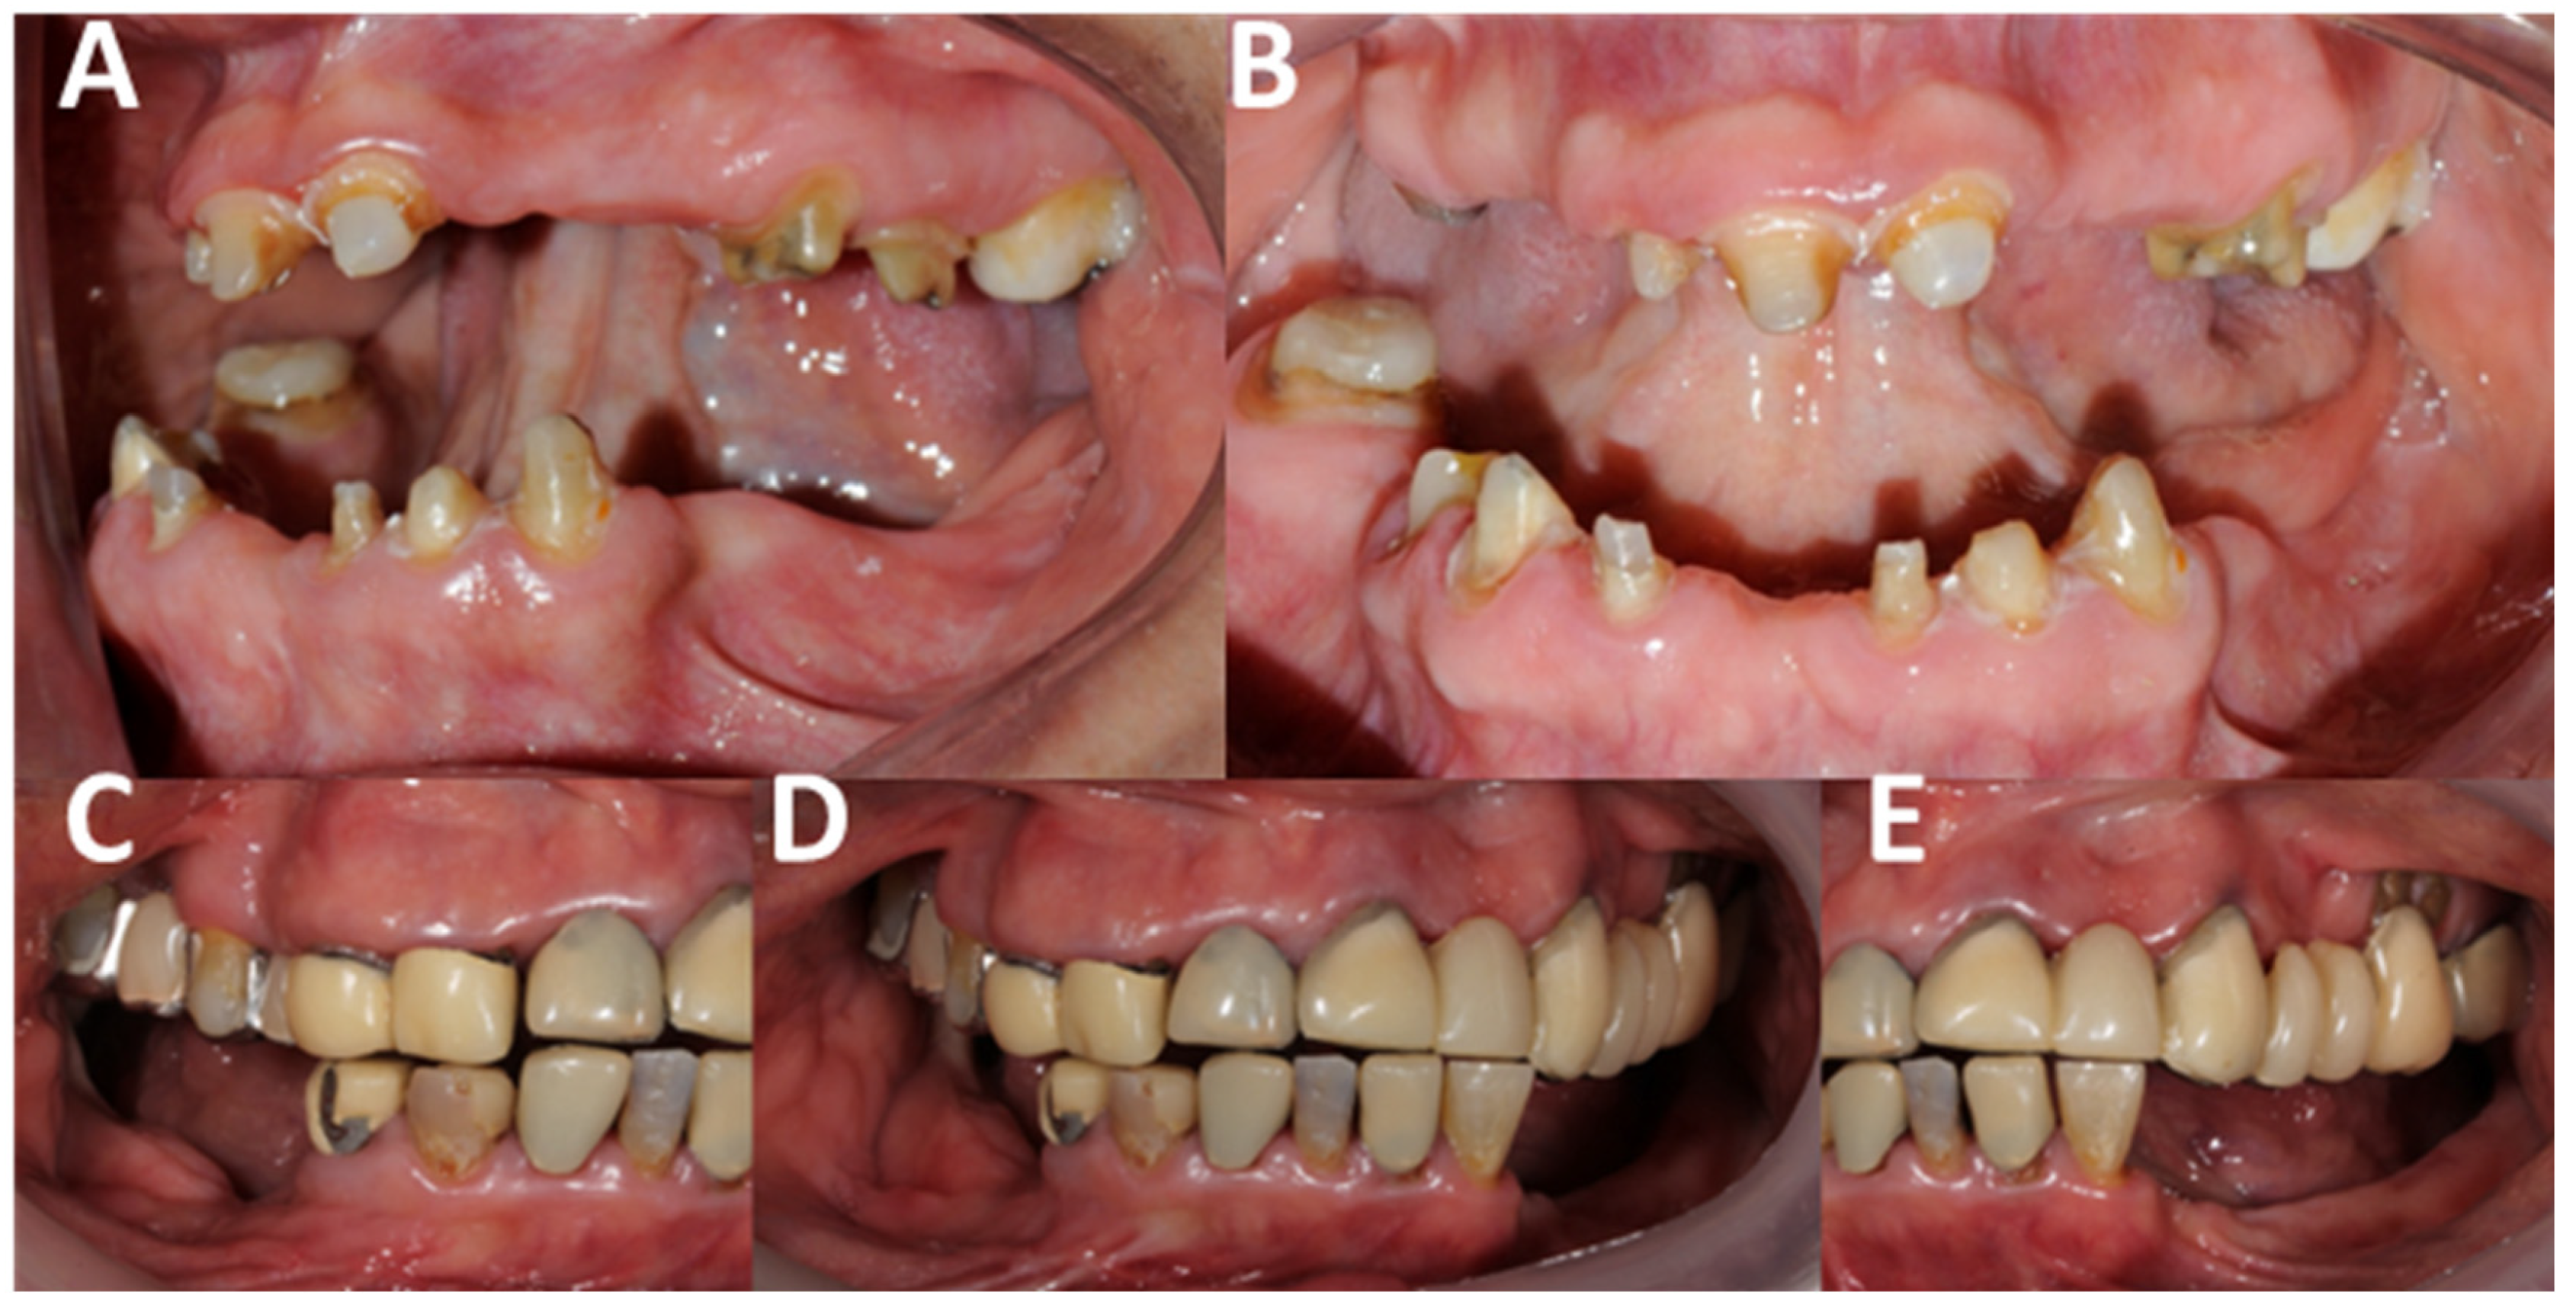

3.3.2. Prosthetic-Level Influences

3.3.3. Hard/Soft Tissue-Level Influences

3.3.4. Dental-Level Influences